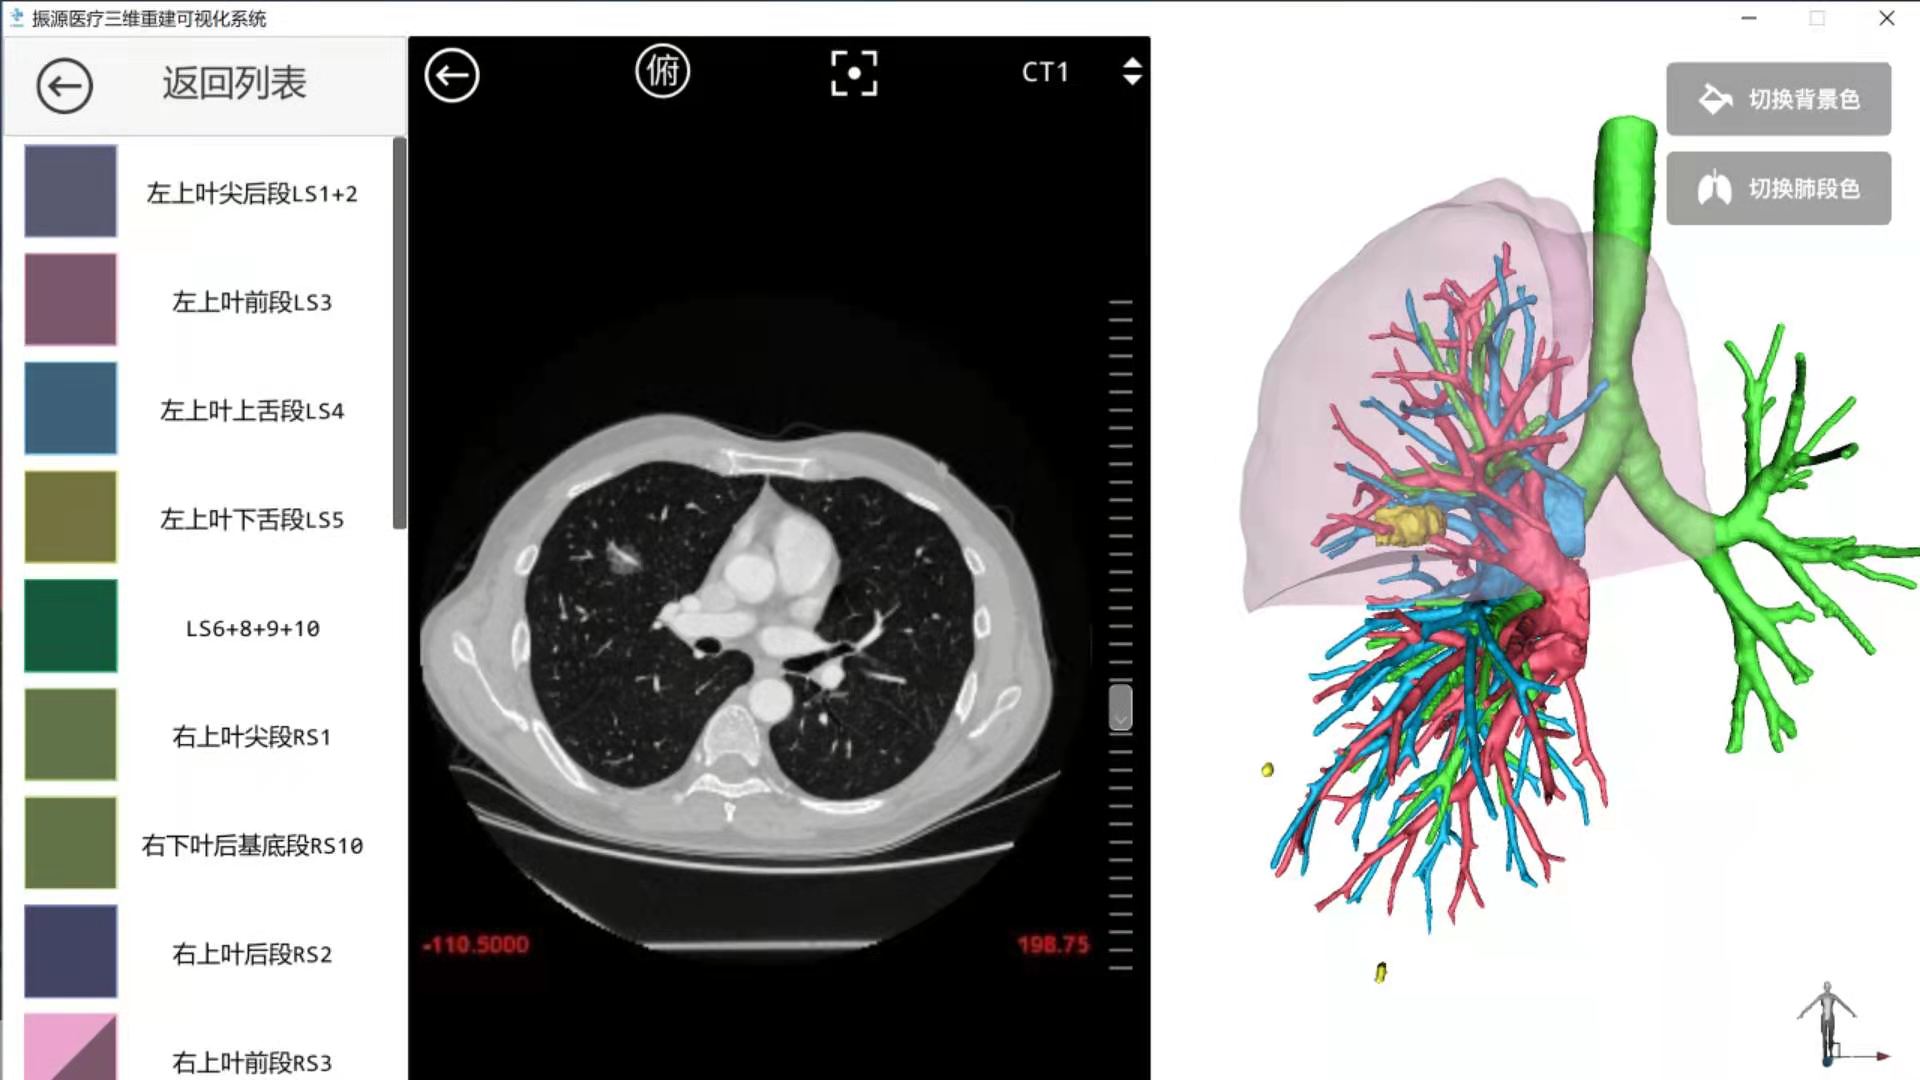

该患者是市公卫中心胸外科收治的一例AIDS合并右肺上叶前段磨玻璃结节的病人,经过完善相关检查,临床考虑早期肺癌,需行手术治疗。术前,通过三维重建,确定了结节的位置、相应肺段的支气管与血管走形,为手术操作提供了清晰的术前规划,拟采取胸腔镜右肺上叶前段切除术。对于肺段之间的术中判定则采取荧光显影技术,这样能够做到精准肺段切除,既能保证结节周围的安全距离,达到完整切除,也能避免切除过多的肺组织,利于患者术后康复,对于患者本人有着莫大的益处。

患者术前CT及三维影像重建

肺癌的早期表现即为肺部结节,精准肺段切除是目前治疗早期肺癌的积极有效手段。通过三维CT重建加胸腔镜荧光显影技术可为临床医生提供更精准的术前模拟规划及术中精准操作,使早期肺癌患者获得最佳的治疗效果。